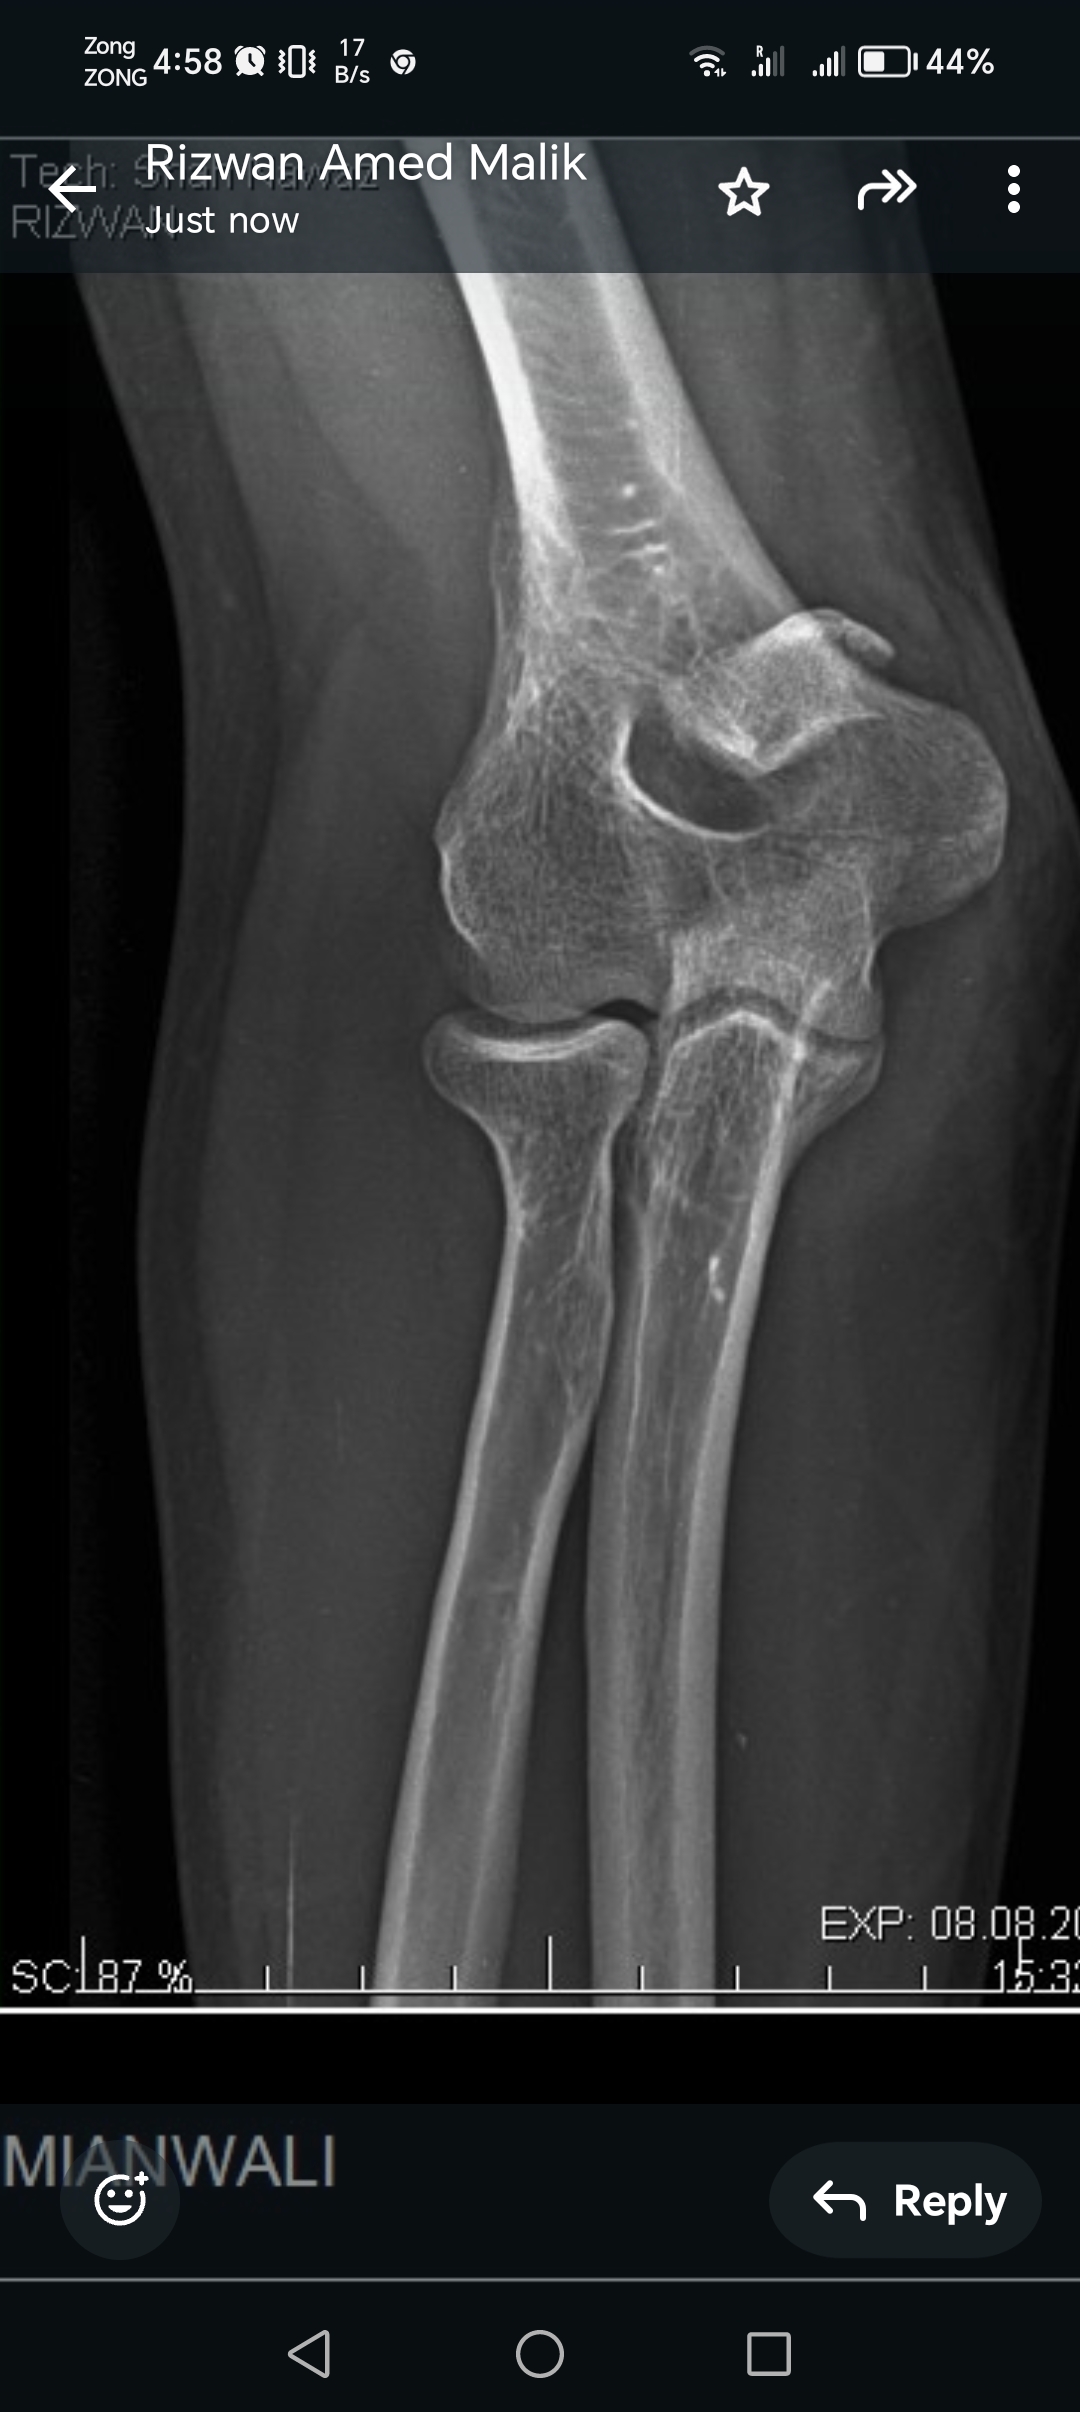

My husband had elbow surgery on 9th of August. I want to know about physiotherapy. When can we start physiotherapy so he can bend and extend his arm freely.Kindly guide us. If we start now will it effect joint or not. TIA